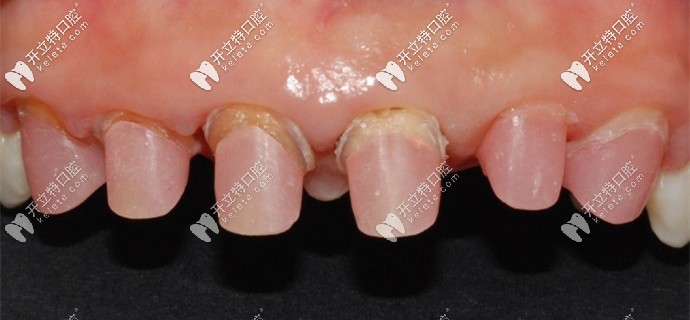

被磨掉1/2的基牙

牙醫(yī)說我的牙齒情況不容樂觀,之前醫(yī)生操作不當(dāng)?shù)脑?,?dǎo)致牙槽骨萎縮、基牙腐爛,只能建議拔掉做種植牙。

我的基牙已經(jīng)腐爛了只能做種植牙